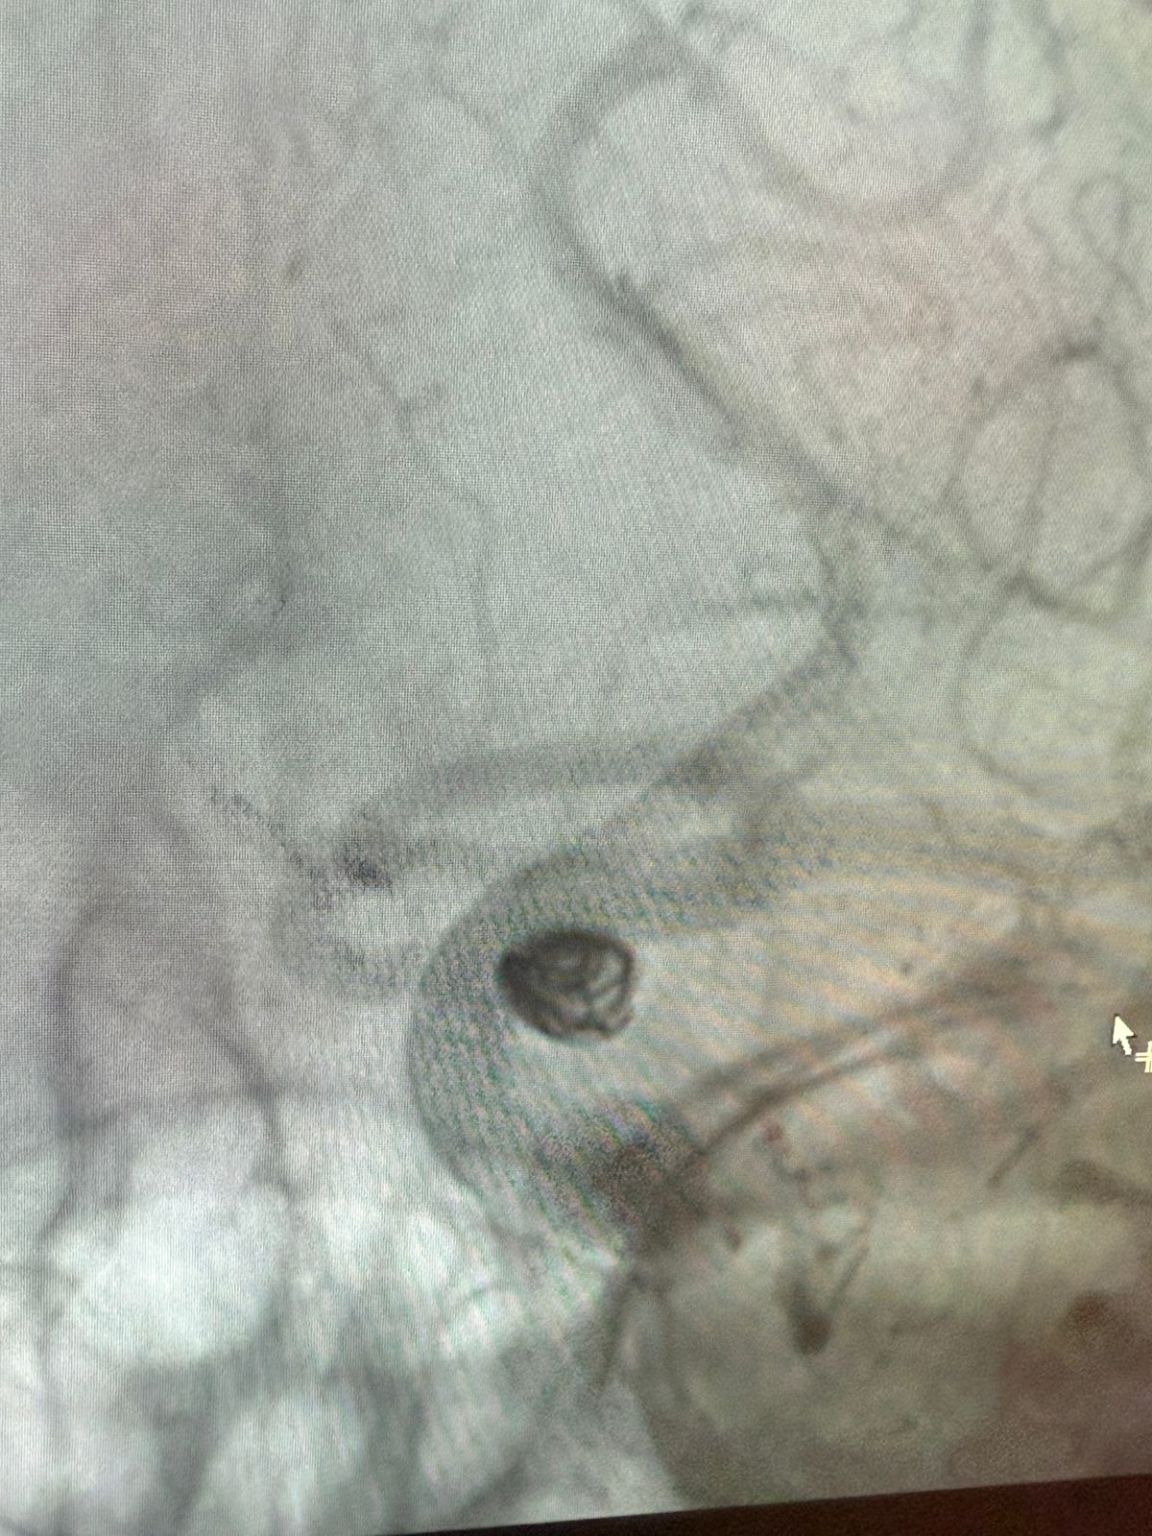

The treatment utilized the Nuva® Flow Diverter (TJED-D 5.0–14), Perdenser® 3D coil, and Frepass® Microcatheter (TJMC18 Plus) for a posterior communicating artery aneurysm.

Dr. Mutis highlighted the excellent visibility of the device and noted that retrieving was smooth. He expressed great satisfaction with the final outcome.